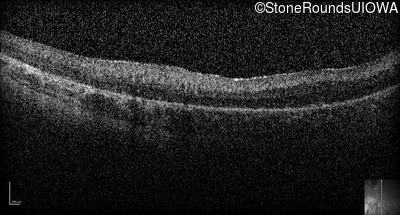

Optical Coherence Tomography - Right -

No Light Perception

Exemplar

Expanded OCT Stack

×